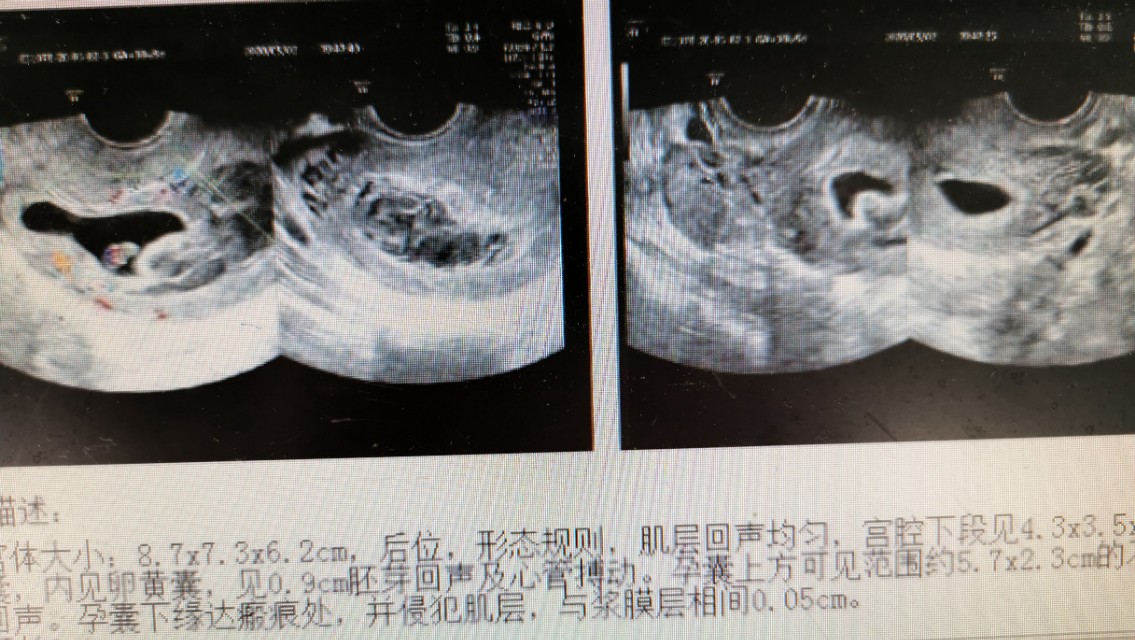

患者今年27岁,停经50天,阴道淋漓出血13天。B超:子宫体大小为8.7×7.3×6.2cm,后位,形态规则,肌层回声均匀,宫腔下段见4.3×3.5×1.9cm的孕囊,内见卵黄囊,见0.9cm的胚芽回声及心管搏动。孕囊上方见范围约5.7×2.3cm的不均质低回声。孕囊下缘达瘢痕处,并侵犯肌层,与浆膜层相间0.05cm。双侧卵巢大小正常。行胸部CT示:右肺上叶感染病灶,多考虑肺结核。患者诊断为瘢痕妊娠合并肺结核。